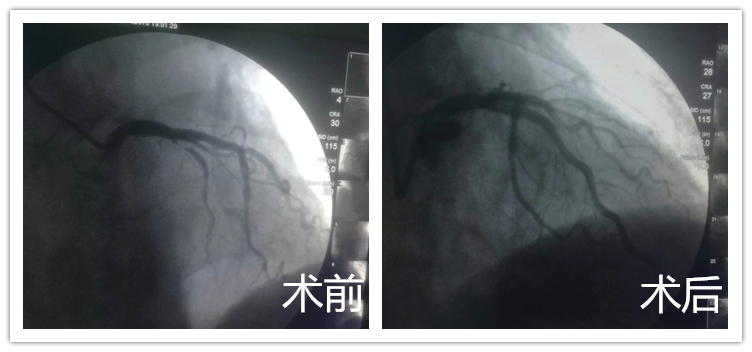

1月26日晚6时左右,87岁高龄的患者范某因突发胸痛2小时无缓解,紧急拨打120送至我院,经急诊绿色通道收治入院,经检查诊断为急性前壁心肌梗死。

患者高龄,进行手术的风险要高出很多,但考虑到时间就是心肌,时间就是生命,主治医生钍戈、主刀医生郑崔成、梁羽积极与家属沟通,耐心为家属讲解病情,最终决定为患者行冠状动脉造影球囊扩张支架植入术。手术全程仅四十分钟,进行顺利,患者愈后良好,无心肌缺血复发,生命体征稳定,术后两三天已能在家人陪同下进行散步。患者家属感慨,我院医疗技术日新月异,突飞猛进,患者未感到任何不适,导丝通过、球囊扩张、支架置入,一气呵成,最短时间完成了手术,把风险降到了最低,术后效果立竿见影,患者生活质量明显提高,患者范某及其家属对心内三科医护人员高超的业务水平和全心全意为患者服务的精神表示了充分的赞扬和肯定。